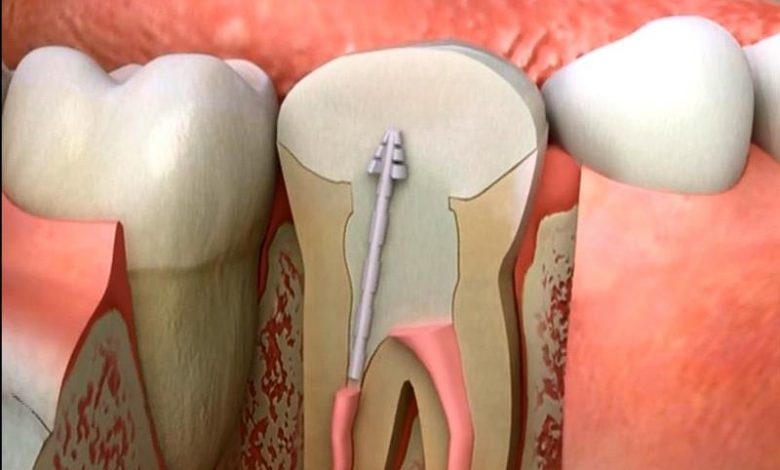

Dişlerin orta kısmında dişözü (pulpa)adı verilen kısım bulunur.Diş özü sinir ve damarlardan oluşan bir yapıdır.Bu yapı dişin duyarlılığını ve beslenmesini sağlar. Diş özü kendini tamir edemeyecek derecede hasar gördüğünde kanal tedavisine ihtiyaç duyulur. Hasara uğramış diş özünün çıkartılıp, yerine yapay maddelerle dolgu yapılmasına kanal tedavisi denir.

Hasar görmüş dişözü çıkarılmazsa diş ve çevresindeki dokular enfeksiyona maruz kalır.Sonunda dişinizi tamamen kaybedebilirsiniz.